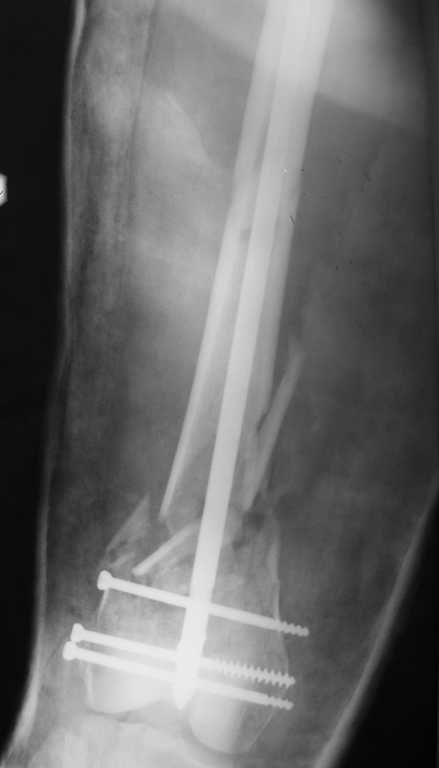

По прямой проекции неплохо. Что за стержень?

Примеры приложены.

И вообще мне кажется, что представленный ОС не допустим:1. стержень в суставе,2. неправильная длинна винтов, 3. ось конечности неправильная, 4. циркулярная гипсовая повязка после ОС?????

-1. стержень в суставе,

Это не критично, в межмышелковой борозде,не на опроной поверхности, выступает из субхондральной кости, не факт что из хряща.Про надколенник Александр Николаевич уже писал.

-2. неправильная длинна винтов,

и толщина тоже. При такой длине хочется помощнее.

-3. ось конечности неправильная,

Вполне прилично. Если в боковой проекции рекувации нет. Где кстати боковая, хочется спросить у постмейкера.

- 4. циркулярная гипсовая повязка после ОС?????

К сожалению, автор умалчивает. Думается, что в данном случае можно и без гипса.

Затем, что результаты как минимум не хуже, чем при использовании глубокоспециализированных DFN. Другое дело, что найти толстый тибиальный гвоздь больше 11м не всегда просто. В показаном примере он бы не подошел. Трочал бы сильнее из колена или при полном погружении отверстия пролетели бы проксимальнее перелома. Он показан больше для нижней трети, чем для области метафиза. Да и желательно чтобы винты толстые были, толще чем для тибии.

Приносим извенения за недостаток информации. Выкладываю все снимки. Стержень фирмы НПО ДЕОСТ(г.Пущино-на-оке)